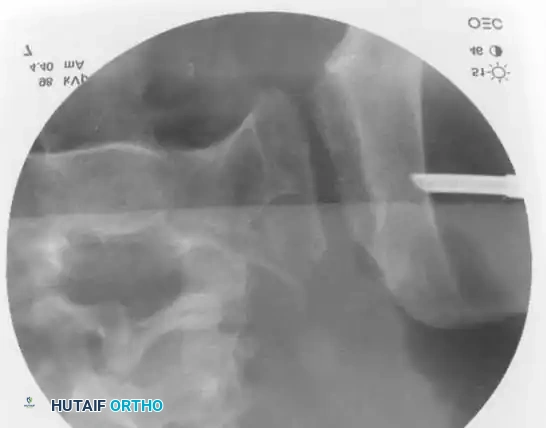

3. Percutaneous Sacroiliac (SI) Screws (Posterior Ring)

The gold standard for posterior ring fixation in appropriately selected patients.

* Indications: Sacral fractures, SI joint disruptions, crescent fractures.

* Technique: Performed under strict fluoroscopic guidance (Inlet, Outlet, and Lateral sacral views).

* Trajectory: The guide wire is advanced from the lateral ilium, across the SI joint, into the S1 (or S2) vertebral body.

* Safety Corridors: The surgeon must possess an intimate understanding of sacral dysmorphism. The "safe zone" is bounded by the sacral neural foramina inferiorly, the spinal canal posteriorly, and the sacral ala anteriorly.

Pitfall: Failure to recognize a dysmorphic sacrum (characterized by upper sacral segment elevation, non-recessed alae, and oblique neural foramina) can lead to catastrophic L5 nerve root injury or vascular penetration during SI screw placement.